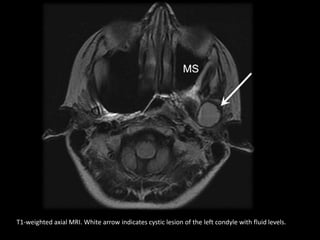

T1-weighted axial MRI. White arrow indicates cystic lesion of the left condyle with fluid levels.

T2-weighted axial MRI. White arrow indicates cystic lesion of the left condyle with fluid

levels. MS, maxillary sinus